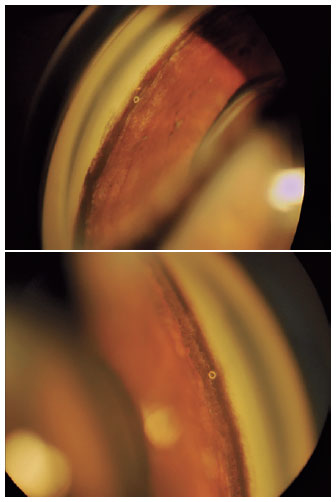

At presentation, she was examined by a uveitis specialist and a rheumatologist, and underwent an extensive laboratory workup to search for rheumatological and infectious causes. All results were normal, and no specific diagnosis was established. Nevertheless, she had IgG antibodies for the herpes simplex virus, varicella-zoster virus, and cytomegalovirus. BADI was suspected, as well as an unusual presentation of bilateral herpetic uveitis. She received oral aciclovir, acetazolamide, and prednisone, besides topical prednisolone, betaxolol, brimonidine, dorzolamide, and atropine bilaterally. After two months, topical corticosteroid was withdrawn, with resumption of symptoms. Prednisolone eye drops were reintroduced and gradually removed over the next two months, as well as all oral medications, with gradual resolution of the disease. Due to persistent ocular hypertension, she was referred to our Glaucoma Department in August 2019. Gonioscopy revealed, bilaterally, a wide and heavily pigmented angle 360°, and a gross pigment deposit in the inferior angle (Figure 2). On fundus examination, the optic discs were normal, with no signs of glaucomatous neuropathy. The IOP was controlled (16/18 mmHg) with three drugs (betaxolol, brimonidine, and dorzolamide). One year after the diagnosis, in April 2020, she developed bilateral cataracts. Combined cataract-iStent® surgery was proposed for both eyes and performed in May and June 2020. The purpose of iStent® implantation was to reduce at least one glaucoma medication. Surprisingly, it was possible to remove all hypotensive agents. At one year after surgery, the IOP was 11/12 mmHg without medication (Figure 3) and visual acuity was 20/15 in both eyes.

02-fig02.jpg)